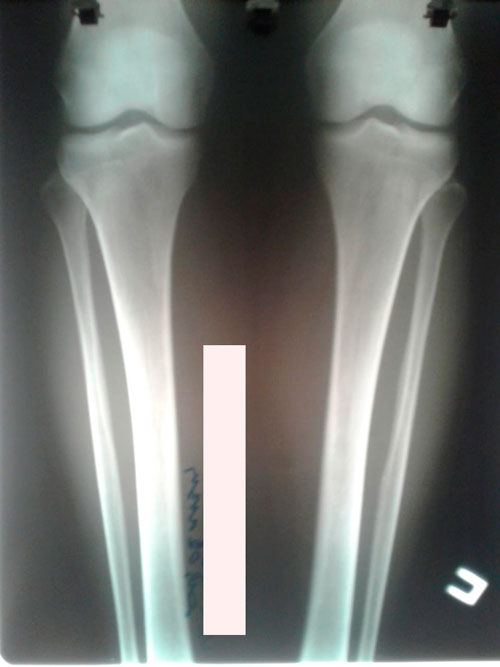

Исходник - 35 лет. Киргизия.

Ротация с обеих сторон.

Дата операции -25.12.2018г.